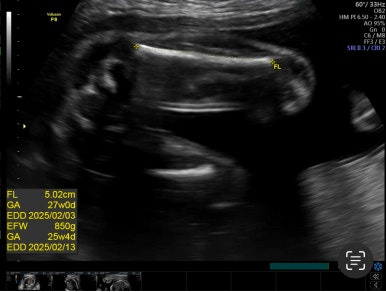

28주 1일

입체초음파로 태아의 얼굴을 볼 수 있는 시기이다!

제일 기다렸던 때이고, 다행히 태아 얼굴을 볼 수 있었다.